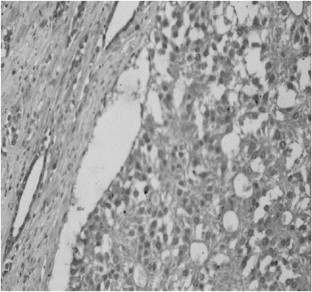

Materials and Methods: We retrospectively analyzed the records on 126 prostate cancer samples from patients treated at our University Hospital from 1995 to 2002. The 72 patients with clinically localized disease (group 1) had undergone radical prostatectomy. Another 54 patients (group 2) had metastatic androgen-independent disease. Archived material relating to the subjects was then immunostained for bcl-2, COX-2 and CD-31, using an anti-bcl-2 monoclonal primary antibody, an anti-COX-2 polyclonal rabbit antibody and an anti-CD-31 monoclonal mouse antibody to evaluate neoangiogenesis (MVD, microvessel density).

Results: We found that bcl-2, COX-2 and MVD expression increased from group 1 to group 2. The intergroup difference was significant only for high MVD (P<0.05). On the other hand, high MVD, high bcl-2 and high COX-2 expression was correlated with a higher PSA level (P<0.01), whereas only a high MVD was also related with Gleason score (P<0.05). We used univariate analysis to evaluate the prognostic impact of biologic and clinico-pathologic parameters on the disease-free-survival of 72 patients treated by radical prostatectomy. A total of 30 patients (41.6%) experienced biochemical relapse; bcl-2, COX-2 and MVD significantly correlated with disease relapse in these patients. In fact, we observed disease relapse in 24/45 (53%) with high bcl-2 expression, in 15/21 (71%) with a high MVD count and finally, in 30/58 (52%) with high COX-2 expression. Finally, PSA value and Gleason score were the only two biologic markers significantly associated to disease relapse in a multivariate analysis.